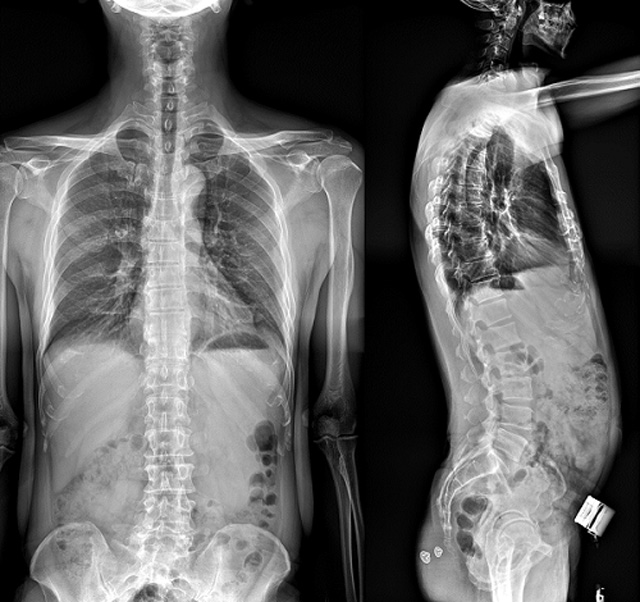

(7)全身拼接功能對(duì)有較大尺寸全脊柱拼接圖接桂成金下股分成幾次拍攝,再經(jīng)過秋件開在骨科開展的全脊柱畸形矯治工作中,雖然CT. MRI也能獲取全脊柱影像,接圖像,以便于長(zhǎng)度、角度、力線等測(cè)量和察脊柱在重力情況下但不能進(jìn)行立位檢查,無法觀全景觀察。全身拼接功能是高等級(jí)DR攝取患者立位全下的功能狀態(tài)圖像,因此采用動(dòng)態(tài)醫(yī)院特別看重的動(dòng)態(tài)DR功能之一。注:圖中Cobb脊柱正側(cè)位圖像是首選的檢查方法角度的大小是反映側(cè)彎嚴(yán)重程度的一個(gè)標(biāo)準(zhǔn)。